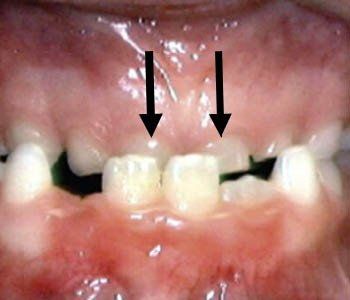

Crowding

There is not enough room in the mouth for all of the teeth to fit so they force space making teeth 'crowd'